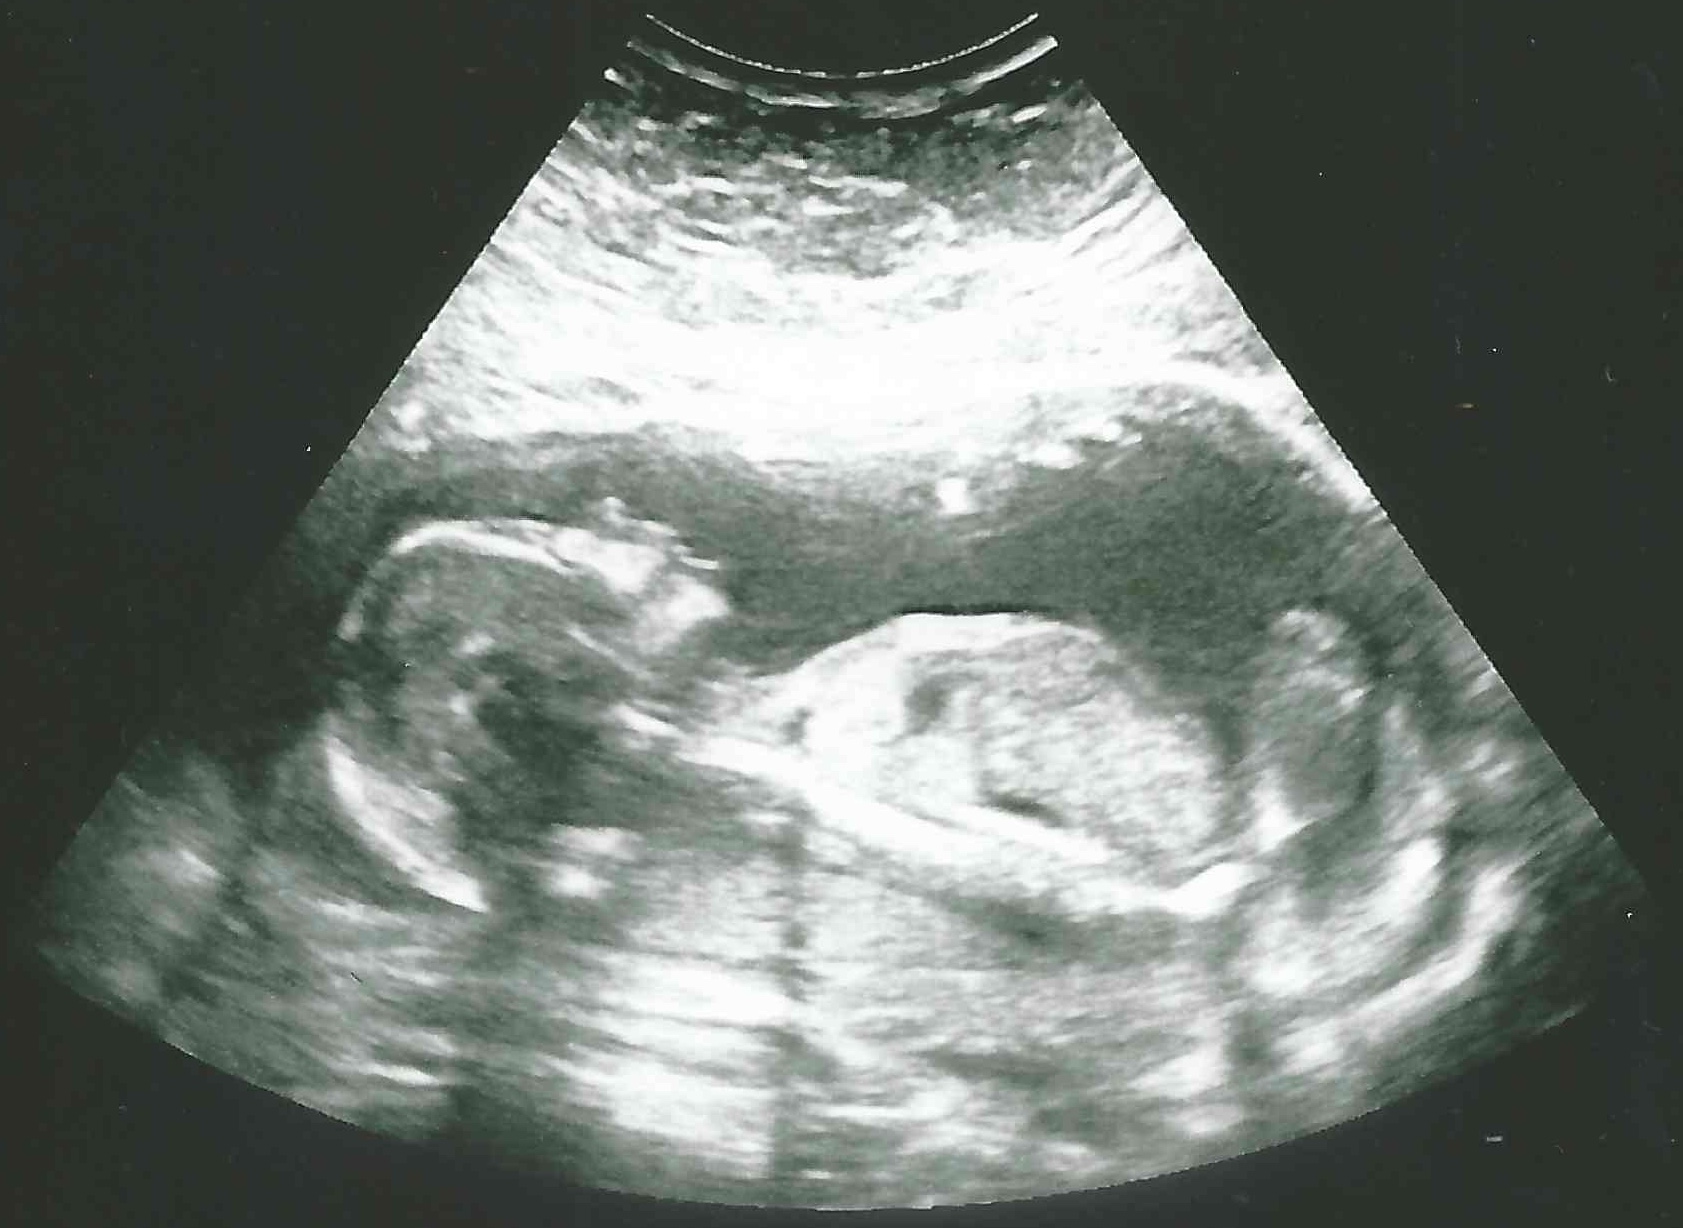

8 weken

12 weken

16 weken

21 weken

25 weken

30 weken

34 weken

37 weken

39 weken